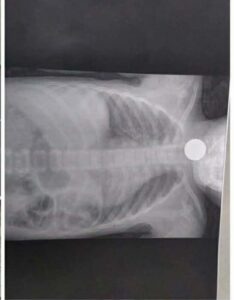

دقه وسرعة إستحابه من الفريق الطبي بقسم الأنف والأذن والحنجرة بمستشفى السنبلاوين العام، بمحافظة الدقهلية، حيث نجح في إنقاذ طفلين شقيقين تعرضا لحالة اختناق حادة بعد ابتلاع عملة معدنية استقرت في البلعوم، ما تسبب في صعوبة شديدة بالتنفس ونوبات كحة متكررة وقيء مصحوب بآثار دم نتيجة احتكاك العملة بالغشاء المخاطي.

وأكد بيان المستشفى، أن الحالتين وصلتا إلى قسم الاستقبال والطوارئ في حالة حرجة، مع ظهور علامات اختناق واضحة، وعلى الفور تعامل الفريق الطبي مع الموقف بشكل عاجل، حيث تم تجهيز غرفة العمليات وإجراء تدخل سريع لاستخراج العملة المعدنية وتأمين مجرى الهواء.

وأضاف البيان أن الفريق الطبي نجح في استخراج العملة المعدنية بالكامل دون حدوث مضاعفات، مع التأكد من سلامة البلعوم والحنجرة، واستقرار العلامات الحيوية للطفلين، وخروجهما من المستشفى بحالة صحية جيدة بعد الاطمئنان الكامل عليهما.